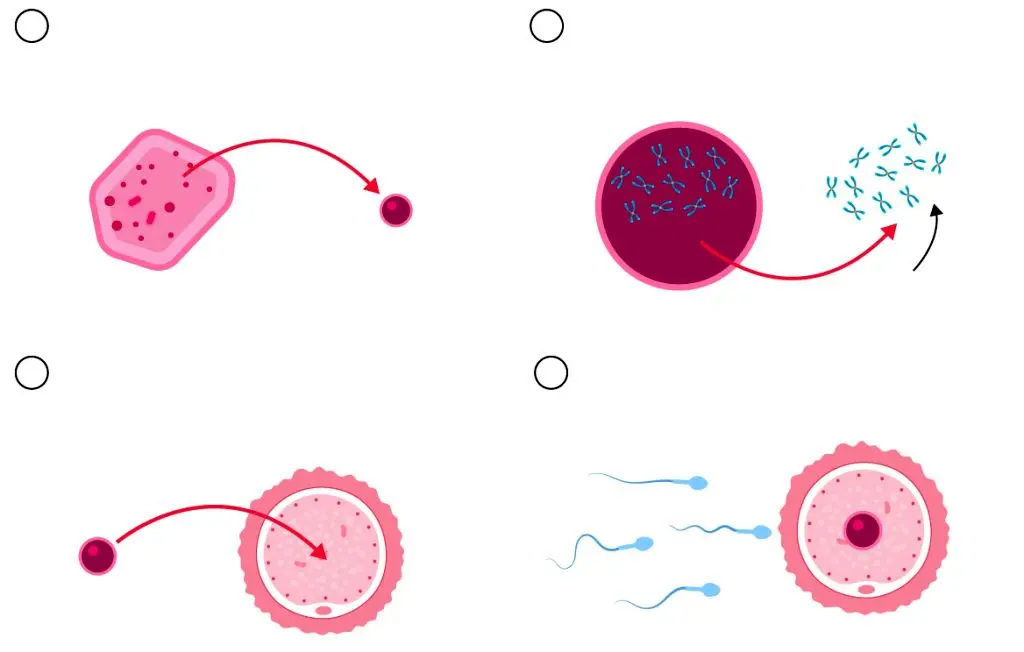

بر اساس مطالعات قبلی، روشی به نام «انتقال سلولهای سوماتیک» میتواند به عنوان یک گزینه جایگزین در نظر گرفته شود. این فرآیند به این صورت است که هسته یکی از سلولهای خود بیمار (مانند سلول پوست) به یک تخمک اهدایی که هستهاش خارج شده، منتقل میشود تا آن سلول بتواند به یک تخمک عملکردی تبدیل شود.

با این حال، در حالی که تخمکهای طبیعی نصف تعداد کروموزومهای معمول (یک مجموعه ۲۳ تایی) را دارند، سلولهایی که از پوست ساخته میشوند، دو مجموعه کروموزوم ( مجموعاً ۴۶ کروموزوم) دارند. بدون انجام هیچ کاری، این موضوع باعث میشود که تخمکهای تولیدشده یک مجموعه کروموزوم اضافی داشته باشند. تاکنون روشی برای حذف این مجموعه اضافی در موشها ایجاد و آزمایش شده، ولی هنوز روی انسانها امتحان نشده است.